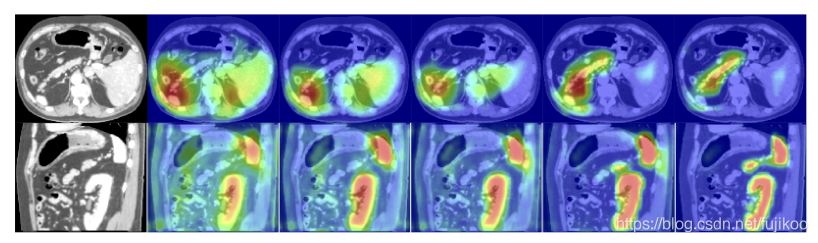

a-e和f-j分别是三维腹部CT扫描的轴位和矢状位视图在经过门前和经过门后的跳跃连接的特征激活图,可以明显看到经过ag之后的效果更好。

图中显示了不同训练epoch中(分别是3,6,10,60,150)的attention coefficients。图像是从测试数据集的三维腹部CT扫描的矢状面和轴向面提取的。该模型逐渐学会关注胰腺、肾脏和脾脏。